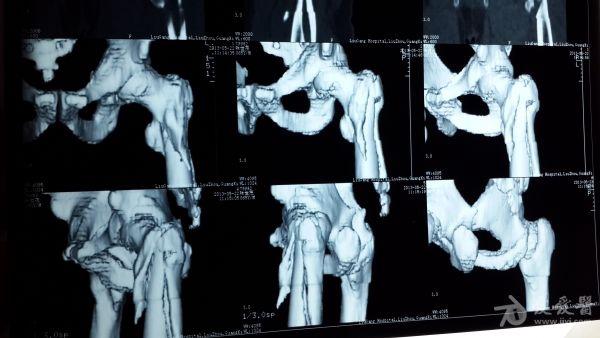

股骨粗隆间粉碎特性骨折的手术方案

男性,65岁

PFNA,闭合复位看看,不行就切开复位加钛l缆

建议使用锁定钢板

γ钉固定,很好!